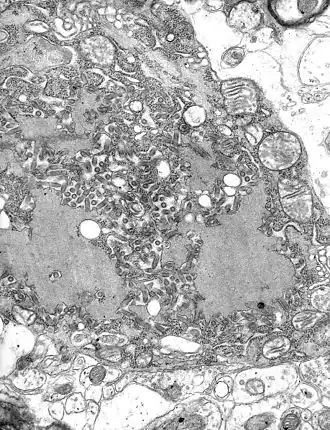

Цистицеркоз является наиболее распространенной предотвратимой причиной эпилепсии в развивающихся странах[70]. Цистицеркоз возникает после приема зараженной пищи, воды или почвы[69]. Кисты и поражения могут вызывать головные боли, слепоту, судороги, гидроцефалию, менингит и слабоумие[71]. Нейроцистоцеркоз, или паразитарная инфекция нервной системы, может привести к летальному исходу. Тениоз не является смертельным. Обычно заражаются после употребления в пищу недоваренной зараженной свинины. Тениоз характеризуется легкими симптомами, включая боль в животе, тошноту, диарею или запор.